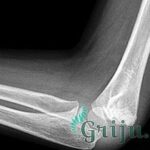

Травмы таранной кости

Поскольку данная кость — самая массивная из всех костей стопы, то ее повреждение проявляется серьезными нарушениями опорно — двигательной системы. По данным медицинской статистики большое количество людей после перелома этой кости становятся пожизненными инвалидами. Такие травмы достаточно редки, но очень серьезны. Так как кости таранного элемента имеют специфическую локализацию и их питают своеобразно расположенные сосуды, то для лечения переломов требуется комплекс специальных мер и длительная реабилитация.

В зависимости от характера механического воздействия различают несколько видов повреждения этой кости. Например, перелом шейки таранной кости, которая является ее самой уязвимой частью, происходит во время чрезмерного сгибания стопы. Чаще такие травмы наблюдаются у спортсменов — атлетов.

При большой нагрузке на стопу или падения с высоты возникает осколочный перелом, при котором наблюдается дробление кости.

Травматизация заднего отростка происходит при интенсивном сгибании ступни, а выворачивание стопы наружу является причиной перелома ее основной части (блока).

При переломе этого анатомического участка происходит нарушение его целостности. При этом поврежденная конечность полностью обездвиживается и становится нефункциональной.